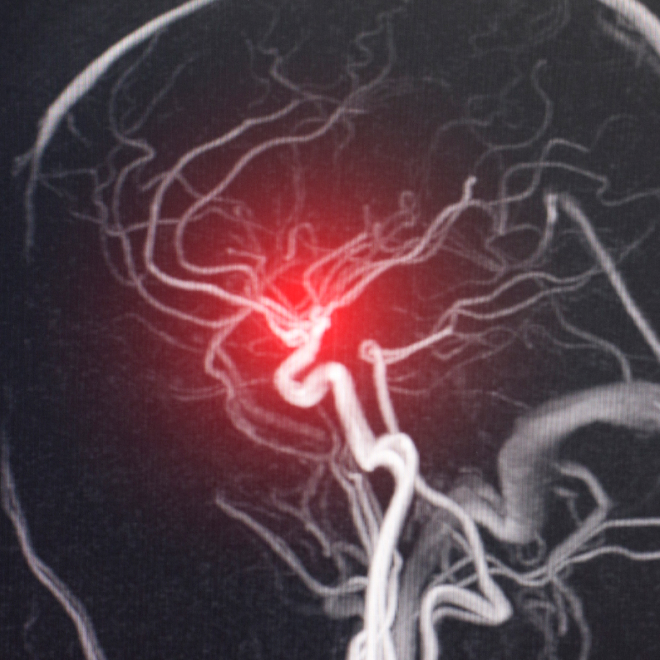

未破裂脳動脈瘤とは

脳動脈壁が部分的に瘤状に膨らみ、破裂しないままの状態であることをいいます。破裂すると、くも膜下出血(破裂動脈瘤)を起こし致死的な症状を発症する危険な血管障害です。人口10万人あたり年間15~20人と言われ、発症年齢は40~60代が最も多くなっています。この脳動脈瘤破裂は、破裂するまで無症状の場合が多く神経症状の警告サインだけでは予測しにくいことが特徴です。

MRA検査 Magnetic Resonance Angiography

おもに、くも膜下出血の原因となる脳動脈瘤発見など、脳血管障害の発見に用いられます。脳血管のみを立体的に抽出する検査で、血管の様子がわかる立体画像を表示することが可能です。血管の狭窄や、梗塞による血流異常、脳動脈瘤の有無などを診断します。